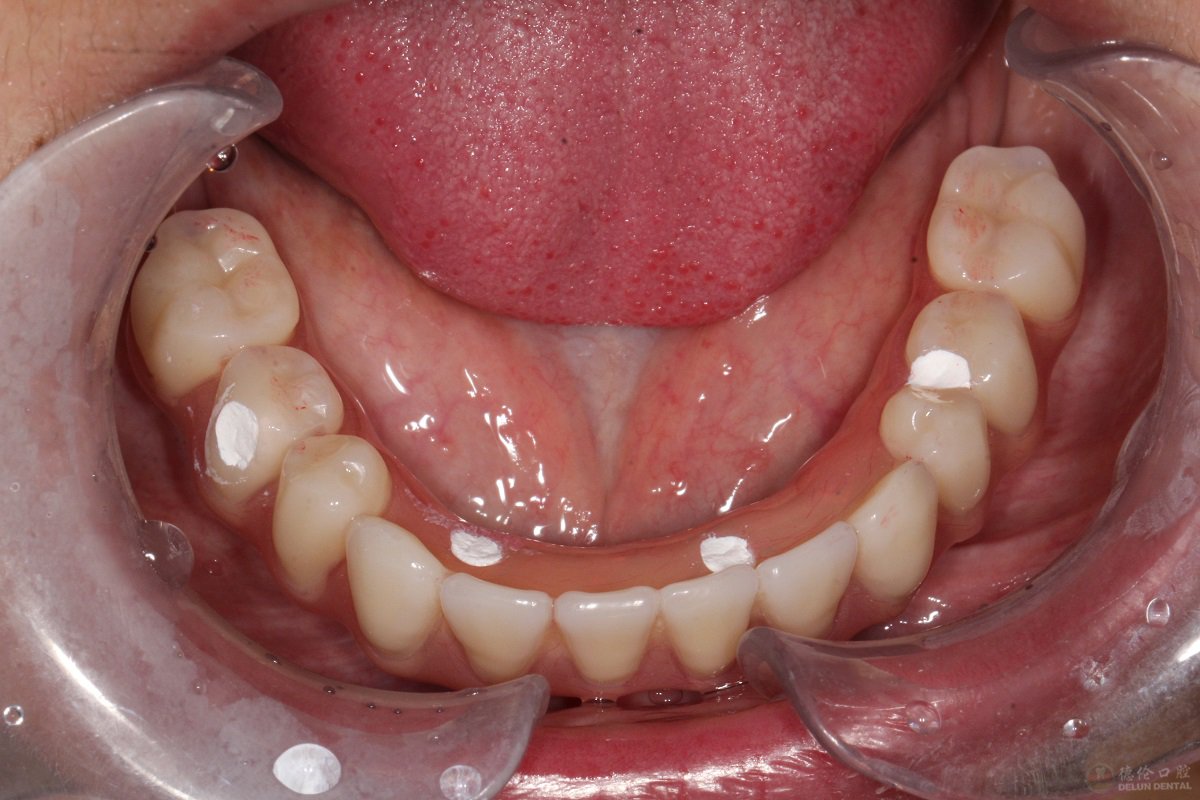

杨女士 70岁

牙齿症状:牙周炎,下颌无牙

修复方式:All—on—4即刻修复

案例经过:30岁开始陆续缺牙,期初采取活动假牙修复,后牙齿越缺越多导致无法正常饮食、睡眠,到我院时下颌只剩3颗摇摇欲坠的牙齿,拔出下颌无法保留的3颗牙后进行半口种植修复。